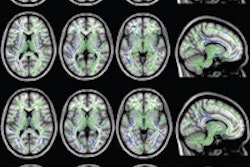

Image shows the neural pathways of the Tasmanian devil (left) and the thylacine, better known as the Tasmanian tiger. Image courtesy of Emory University.